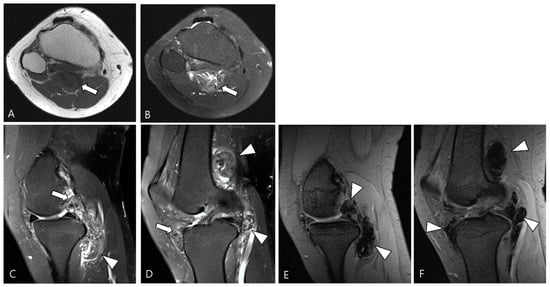

2.4. Relationship to Adjacent Structures of D-TSGCT

3.2. Differential Diagnoses of Extra-Articular D-TSGCT

3.2.1. Fibroma of the Tendon Sheath (FTS)

3.2.2. Extra-Abdominal Desmoid-Type Fibromatosis (DF)